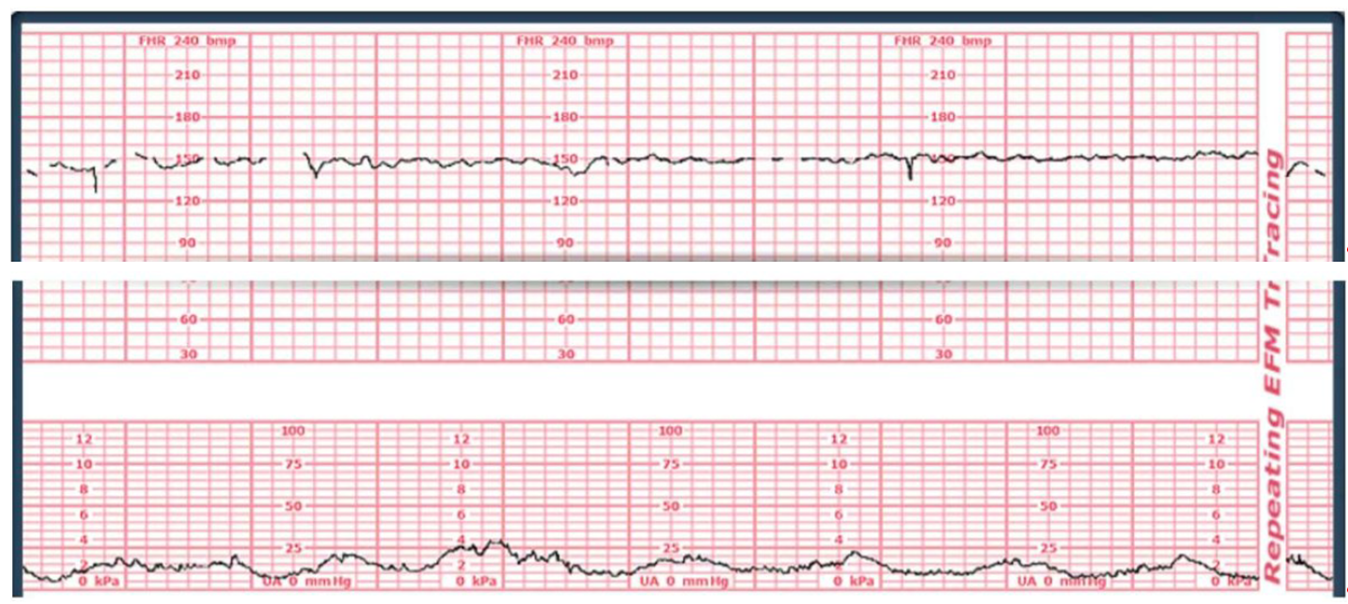

A 37-week client is stating she is having severe back pain and is placed on an external monitor. The monitor shows the following fetal and contraction tracing.

How would the nurse document the client's contractions?